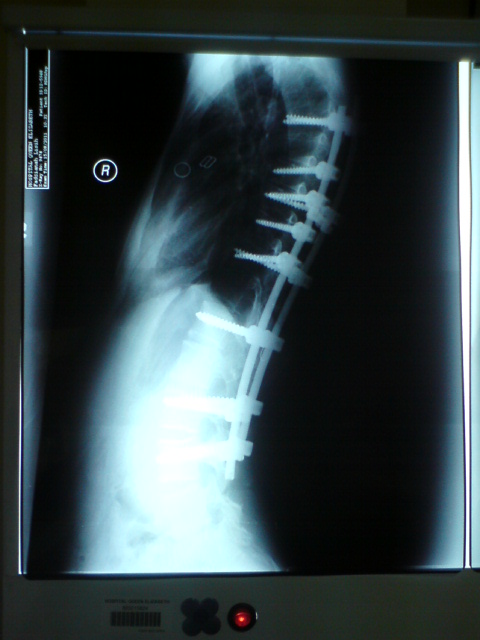

(Red Marks) skru kiri paling atas~terkena saraf

ok! doc ckp, semua ok...tiada masalah...yang paling menyeronokkan..doktor Fadz tanya Fadz, kalau nak ambil gambar x-ray tu..Fadz cakaplah yang Fadz nak ambil gambar...hehehe..dapat juga gambar x-ray yang terang...

~I Like my Spine~

~I LOVE MY SCREWS~

sekarang ni.."bengkak" kat belakang masih lagi timbul...masa last appoiment tulang dulu, doktor cakap, bengkak tu takkan dapat reda lagi..sebab degree curve dulu teruk sangat..(80degree)..so, akan susah untuk dapat body macam dulu..body sekarang memanglah lurus, tapi, pandangan sisi pula macam mana??lepas tu kalau tunduk, macam org bongkok...